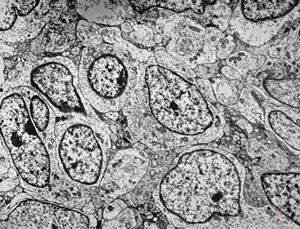

F,3y. | toxoplasmosis